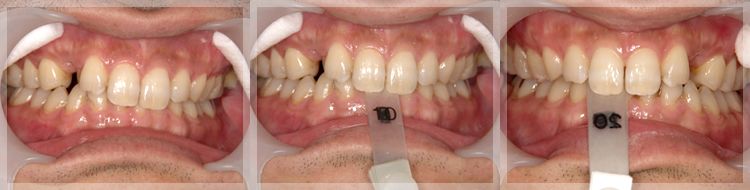

すれ違い咬合の改善

術前 | 術後 |

---|---|

![]() ![]() ![]() |